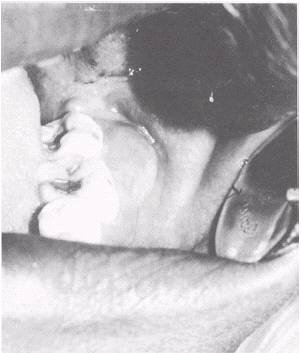

PERICORONITIS

Pericoronitis is an inflammation of the gingiva around a partially erupted tooth. The mandibular third molars are most often affected, although any erupting tooth may be involved. In the mouth of a young adult, part of a tooth can be seen projecting through the gingiva, usually distal to the second molar. The surrounding tissues are usually acutely inflamed. The inflammation may be caused by irritation resulting from the patient's inability to keep the area properly cleansed. Another cause of inflammation is infection from oral pathogens that gained access to the tissues surrounding the crown of the erupting tooth through the opening made by a projecting tooth cusp. The "gingival flap" may become infected after inflammation as a result of the constant irritation caused by contact with the occlusal surface of an erupting maxillary third molar.